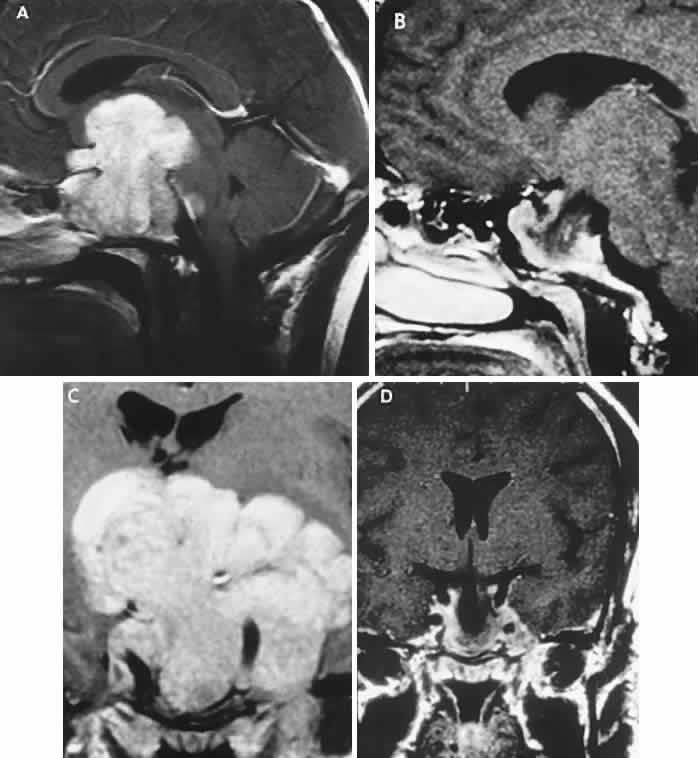

Fig. 2. Large prolactinoma. Original vision in the right eye (RE) was 8/200, left eye (LE) 1/200, with serum prolactin of 26,000 ng/ml and galactorrhea. Four months of bromocriptine reduced prolactin to 661 ng/ml, vision improved to RE 20/40, LE 20/50. At 3 years, vision was as follows: RE 20/30, LE 20/20; prolactin was 25.9 ng/ml. Enhanced magnetic resonance imaging. Sagittal (A) and coronal (C) images at diagnosis. Sagittal (B) and coronal (D) images at 2-year follow-up, showing dramatic shrinkage of the mass.

The absence of field defects, for example, in patients undergoing evaluation for amenorrhea, galactorrhea, or sellar enlargement incidentally discovered, does not imply the absence of an adenoma. Obviously, patients with microadenomas, that is, confined within the sella, do not have field defects. From a study24 of 50 cases of pituitary adenomas with chiasmal syndrome, it was concluded that visual disturbance occurs when the chiasm is displaced approximately 10 mm upward (see also Volume 2, Chapter 4, Fig. 6). The modern management of pituitary adenomas should involve several disciplines: current neuroradiologic studies detect microadenomas and provide precise delineation of gross morphology and status of neighboring structures, and mixed MRI signals suggest new or old hemorrhage, cysts, and so forth (Fig. 2); radioimmunoassay techniques assay PRL and other endocrine levels; oral neuropharmacologic agents, such as bromergocryptine, provide a “medical adenomectomy” for hyperprolactinemia and acromegaly; transsphenoidal surgery, including high-illumination microscopical procedures, televised radiofluoroscopic monitoring, and infection control, has all but replaced transcranial approaches; immunohistochemistry techniques have replaced the anachronistic tinctorial designations (e.g., chromophobe, basophilic) with a functional classification.